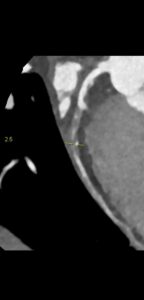

Figurile 6 si 7: reconstrucție multiplanară din examinarea inițială cu evidențierea stenozei severe de la nivelul arterei circumflexe, ce a fost stentată ulterior

Figura 8: reconstrucție volumică (VRT) din examinarea inițială cu evidențierea stenozei severe de la nivelul arterei circumflexe